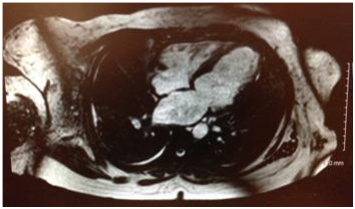

Physical Examination revealed tachycardia with displaced point of maximal impulse (PMI) and minimal rhonchi on right lung base. Laboratory workup did not show any significant results on presentation. Chest X-ray showed bilateral interstitial infiltrates with areas of fibrosis and the chest CT Angiogram (Figure 1) showed bilateral scattered pulmonary nodules and densities, a right-sided pleural effusion, pleural thickening and cardiomegaly.

Figure 1 Computed Tomography scan of the chest showing right side pleural effusion, pleural nodules and densities.